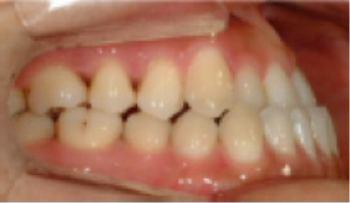

• 하악 전돌(주걱턱) 아래턱이 앞으로 나옴.

Before

After